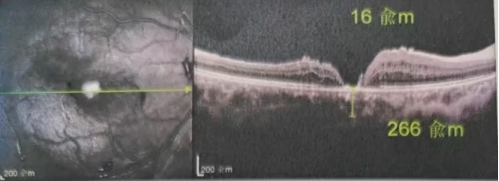

【文章導(dǎo)讀】去年年底,年逾7旬的吳爺爺突然發(fā)現(xiàn)右眼看不清,且看東西變形,到當(dāng)?shù)蒯t(yī)院檢查后確診黃斑裂孔。此后他輾轉(zhuǎn)求醫(yī),經(jīng)歷了兩次玻切聯(lián)合內(nèi)界膜剝除術(shù),每次術(shù)后都嚴(yán)格趴睡一個(gè)月。

去年年底,年逾7旬的吳爺爺突然發(fā)現(xiàn)右眼看不清,且看東西變形,到當(dāng)?shù)蒯t(yī)院檢查后確診黃斑裂孔。此后他輾轉(zhuǎn)求醫(yī),經(jīng)歷了兩次玻切聯(lián)合內(nèi)界膜剝除術(shù),每次術(shù)后都嚴(yán)格“趴睡”一個(gè)月。然而結(jié)果令人失望:裂孔不但沒閉合,反而持續(xù)擴(kuò)大,甚至還并發(fā)高眼壓。

由于自身患有頸椎病,每次術(shù)后長(zhǎng)期的趴睡都讓他痛苦不堪。為了尋求更好的治療,吳爺爺來到廈門大學(xué)附屬廈門眼科中心,找到了眼外傷及眼底病2科的李海波博士后。此時(shí),吳爺爺右眼的黃斑裂孔已經(jīng)持續(xù)擴(kuò)大到780μm,演變?yōu)殡y治性的大裂孔。

最讓吳爺爺難以置信的是:術(shù)后只需保持平躺24小時(shí)!第二天復(fù)查時(shí),眼底鏡及OCT檢查清晰顯示——那個(gè)折磨了他大半年的大裂孔,竟然閉合了!且吳爺爺?shù)挠已垡暳τ辛嗣黠@的改善,術(shù)后3天已經(jīng)可以看到 0.15。